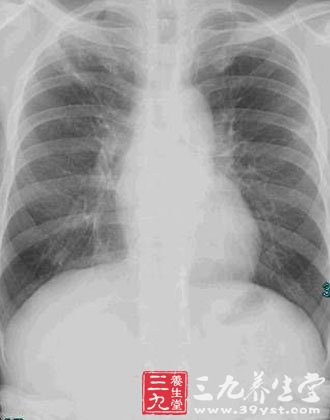

(1)常规X线胸片 摄片技术须注意穿透条件适当,应用中度增感屏,聚焦要小。早期肺泡炎X线上不能显示异常;随病变进展,X线表现出云雾状、隐约可见微小点状的弥漫性阴影,犹如磨玻璃。进一步进展则见纤维化愈趋明显,从纤细的网织状到粗大网织状,或呈网织结节状。晚期更有大小不等的囊状改变,即蜂窝肺。肺容积缩小,膈肌上抬,叶间裂移位。

(2)CT 对比分辨率优于X线,应用高分辨CT(HRCT)可以进一步提高空间分辨率,对于IPF的诊断,特别是早期肺泡炎与纤维化鉴别以及蜂窝肺的发现极有帮助。